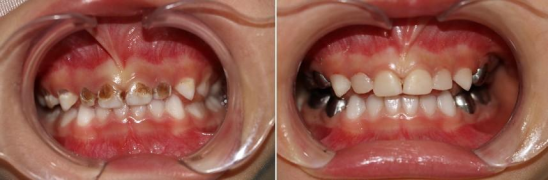

擅长儿童龋病的综合防治,儿童牙髓病、根尖周病的诊疗,不合作儿童的行为诱导和镇静,全麻下儿童牙齿治疗。

她积极学习和引进国内外的新技术和新项目,和麻醉科、手术室进行多学科合作,率先在91直播

开展舒适化儿童口腔治疗技术,使患儿能够更好的接受治疗,在诊疗的过程中做到人性化、无痛化、舒适化。